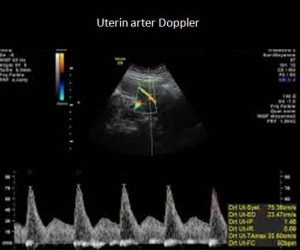

السيطرة على نمط تدفق المقاومة المنخفضة التي توفر تدفق الدم السهل في الشريان السري الشرايين الرحمية هي الأوعية التي تحمل الدم إلى الرحم (الرحم). يتحقق فحص دوبلر للشريان الرحمي من وصول كمية كافية من الدم إلى المشيمة.

يحتاج الطفل إلى الكثير من العناصر الغذائية والأكسجين لينمو بمعدل صحي. لذلك ، يجب أن تكون جدران الشرايين الرحمية مرنة للسماح بمرور أكبر قدر ممكن من الدم. تتوسع هذه الشرايين ، التي عادة ما تكون صغيرة ، أثناء الحمل للسماح لمزيد من الدم بالوصول بسهولة إلى الرحم. وبالتالي ، يتم تشكيل نمط تيار منخفض المقاومة. التدخين وشرب الكحول وتناول بعض الأدوية وما إلى ذلك. تؤثر عوامل نمط الحياة مثل تدفق الدم عن طريق زيادة مقاومة الشرايين.

فحص دوبلر الشريان الرحمي: الشرايين الرحمية هي أوعية دموية تنقل الدم إلى الرحم. عادة ، هذه الشرايين صغيرة الحجم. لكن أثناء الحمل ، يزداد حجم هذه الشرايين (تتوسع) لتوفير مقاومة أقل وبالتالي السماح بتدفق المزيد من الدم من خلالها. يساعد فحص دوبلر في هذه المنطقة على التحقق مما إذا كان الدم الكافي قد وصل إلى الرحم.